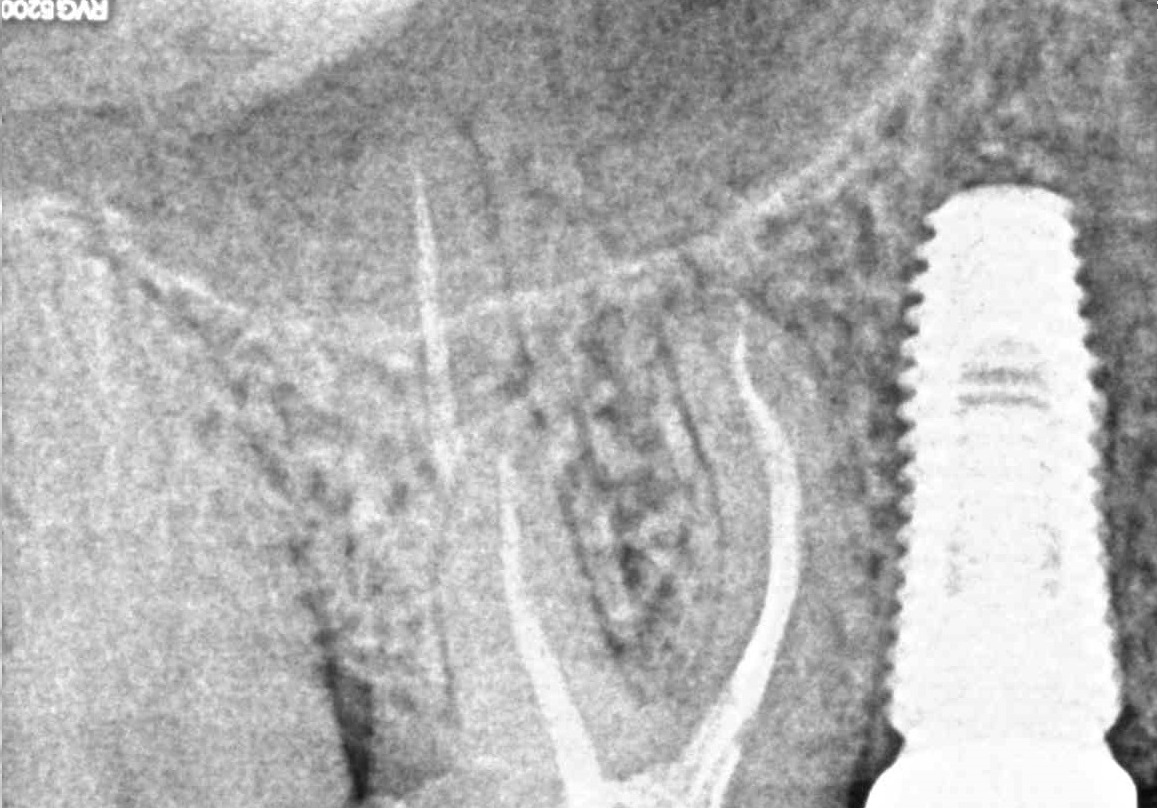

- Лечение периодонтита

Проблема

Пациент обратился в клинику с постоянными ноющими болями усиливающимися при накусывании.Решение

В нескольких клиниках было предложено удаление данного зуба. В нашей клинике такие зубы лечат. Пациенту было проведено эндодонтическое лечение данного зуба. Результат положительный, идет восстановление костной ткани.Оставьте заявку - перезвоним в течении 15 минут!